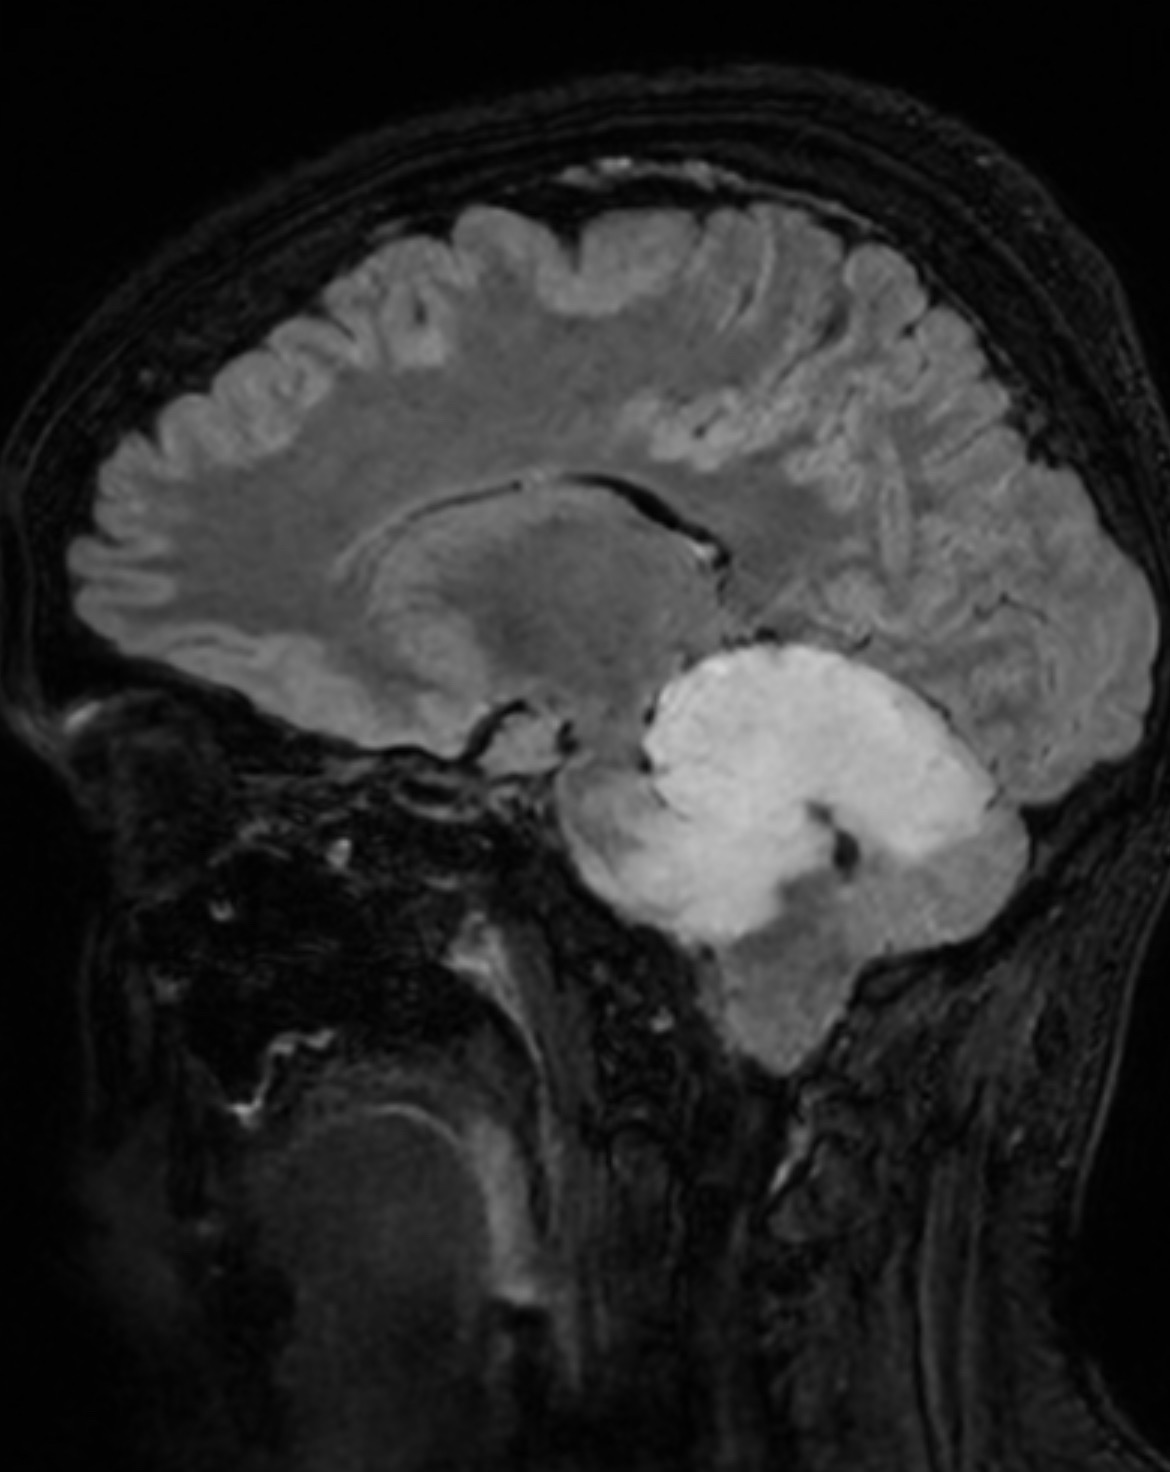

I’ve been avoiding make this it because I struggle with asking for help, but as a few of you know I was diagnosed with a type of brain cancer called IDH-mutant Astrocytoma at the beginning of this year.

I have been in treatment since April, and did 33 rounds of radiation, and 6 months of chemotherapy which I will finish in December. I will not be cancer free with treatment but it will hopefully slow down my tumor growth and I am unable to have it removed due to it being located against my brain stem.